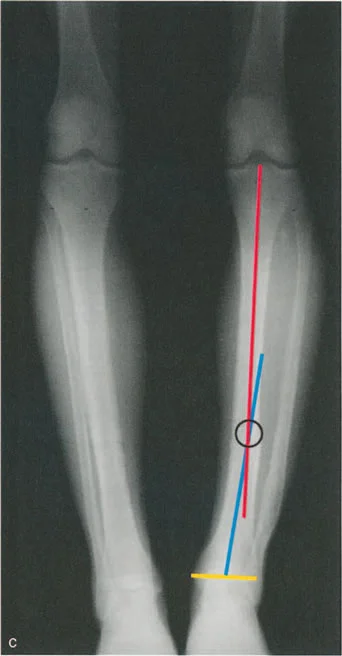

تقوس وفحج الجزء البعيد من عظم الساق

تتحدد درجة الشذوذ في المشي في تشوهات المستوى الأمامي للج